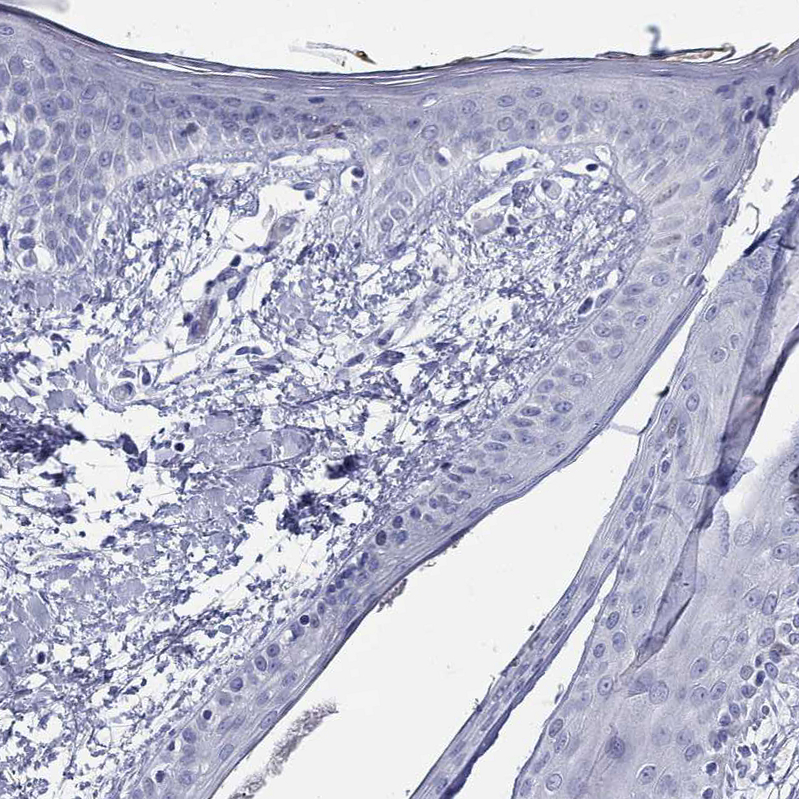

Immunohistochemical staining of human caudate nucleus shows moderate positivity in synapses and neuronal projections.